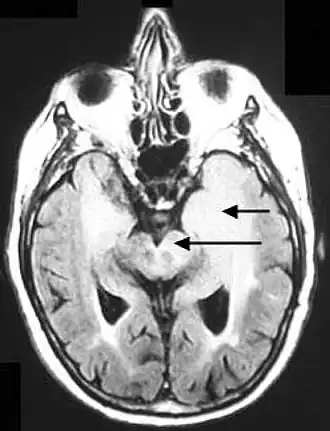

Gliomatose cérébrale

La gliomatose cérébrale ou astroblastome décrit la croissance envahissante de cellules neuroépithéliales qui ont la capacité de se différencier en neurones, en oligodendrocytes et en astrocytes. La majorité des tumeurs cérébrospinales sont d'origine neuroépithéliale[1].

Les conférences de consensus d'anatomopathologistes réunies par l'Organisation mondiale de la santé (OMS) retiennent comme définition d'une gliomatose cérébrale l'infiltration néoplasique diffuse de la glie d'au moins trois lobes cérébraux, impliquant les deux hémisphères ou la matière grise plus profonde[6],[7],[8].